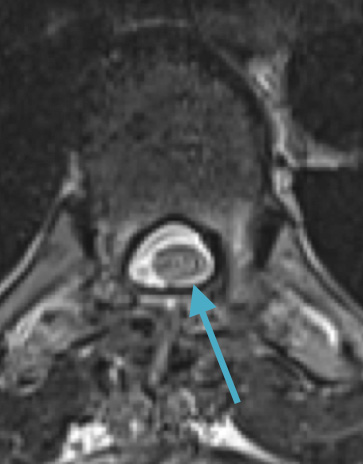

Postoperative MRI T2 illustrating the restoration of CSF surrounding the cord (blue arrow)